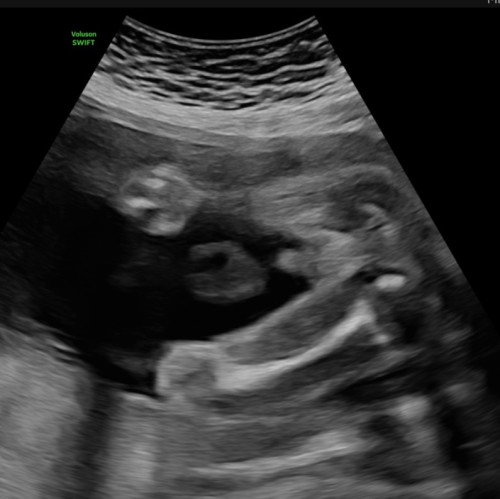

hai mommy2 ,dri gmbar ni dr ckp bby boy.. cuma nk tnya laa pnglaman ada ke mommy2 yg pnh dpt gmbar hasil mcm ni tp nt kluar girl 😅 atau memng jelass da yg ni boy ? 🥹 sbb kita da ada twin girl da 😅 tu excited skitt bila thu boy klau betul boy Alhamdulillah syukur 🙈

CONFIRM BOY 😍😍 anak saya dua dua boy mcmtu la hihi

sah boy.saya 4 dah boy..semua gini

cam jelas sangat je tu boy 😆

jelas sgt tu sis..boy.tahniah.

ni dh confirm boy ni